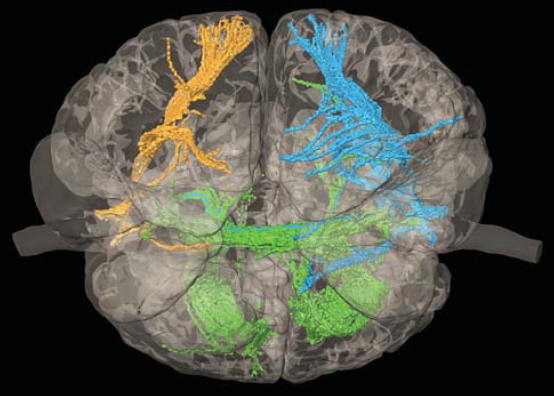

5 ábra.

A traktrográfia alapján készült 3D modell mutatja az agyak, illetve a pályarendszerek helyzetét.

Az MRI leletek alapján traktográfiás elemzés is történt (5. ábra). Ennek lényege, hogy a vízmolekulák mozgása az idegrostok lefutása irányában történik, így MRI segítségével lehetővé válik az ideg-rosthálózat képalkotó vizsgálata. E célból 3D nyomtatásos modelleket is készítettek. A vizsgálat célja volt kideríteni, hogy a két agy összenövése helyén, az interthalamikus híd átvágása esetén, milyen károsodásra számíthatnak. Több konzílium alapján Csókay véleménye az volt, hogy extrapyramidális mozgászavar várható, amely azonban későbbi mozgásterápiával javítható lesz.

6/a,b. ábra.

3D nyomtatott modellek.

Elkészítették a teljes agyak 3D modelljét is, amelyen az idegsebészek gyakorolhatták a szétválasztó műtétet. Más modelleken, - s ez a plasztikai sebészek későbbi segítségére volt-, a megnövelt koponyabőr megfelelő lebenyekre lett osztva, amelyekkel szimulálhatták, hogy a növesztett bőr tényleg befedi-e majd mindkét koponyadefektust (6/ a-b. ábra).